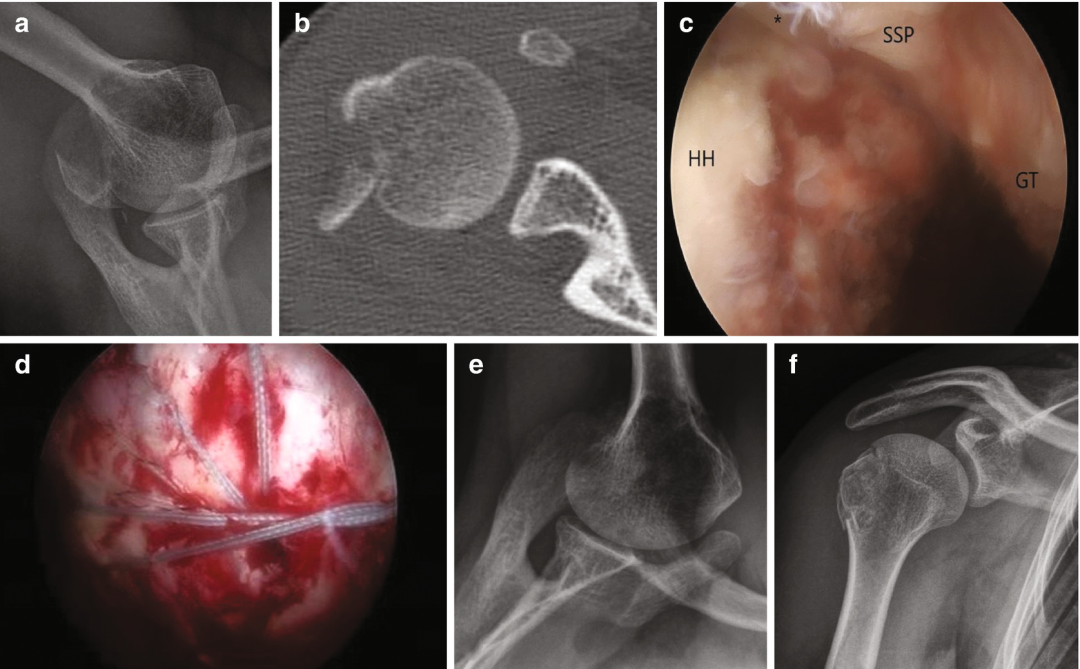

图8 大结节移位骨折的影像学与术中技术图示

常规腋位X线片(图a)及CT扫描(图b)显示肱骨大结节(GT)移位性骨折。术中可见冈上肌肌腱(SSP)及冈下肌肌腱骨性撕脱(图c)。采用双排经骨等效缝合桥技术固定骨折块:内侧排使用2枚缝合锚钉,外侧排应用2枚无结锚钉(图d)。术后X线显示腋位(图e)及前后位(图f)骨折解剖复位。